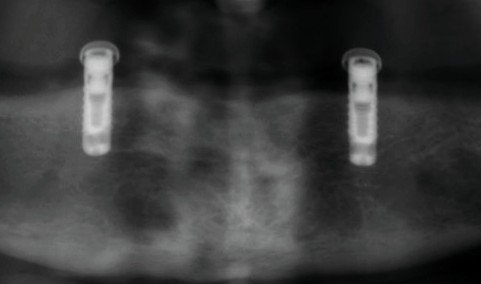

Quiero cambiar pilares locators y teflones de ambos implantes, pero desconozco la marca. Podrían ayudarme? Gracias de antemano.